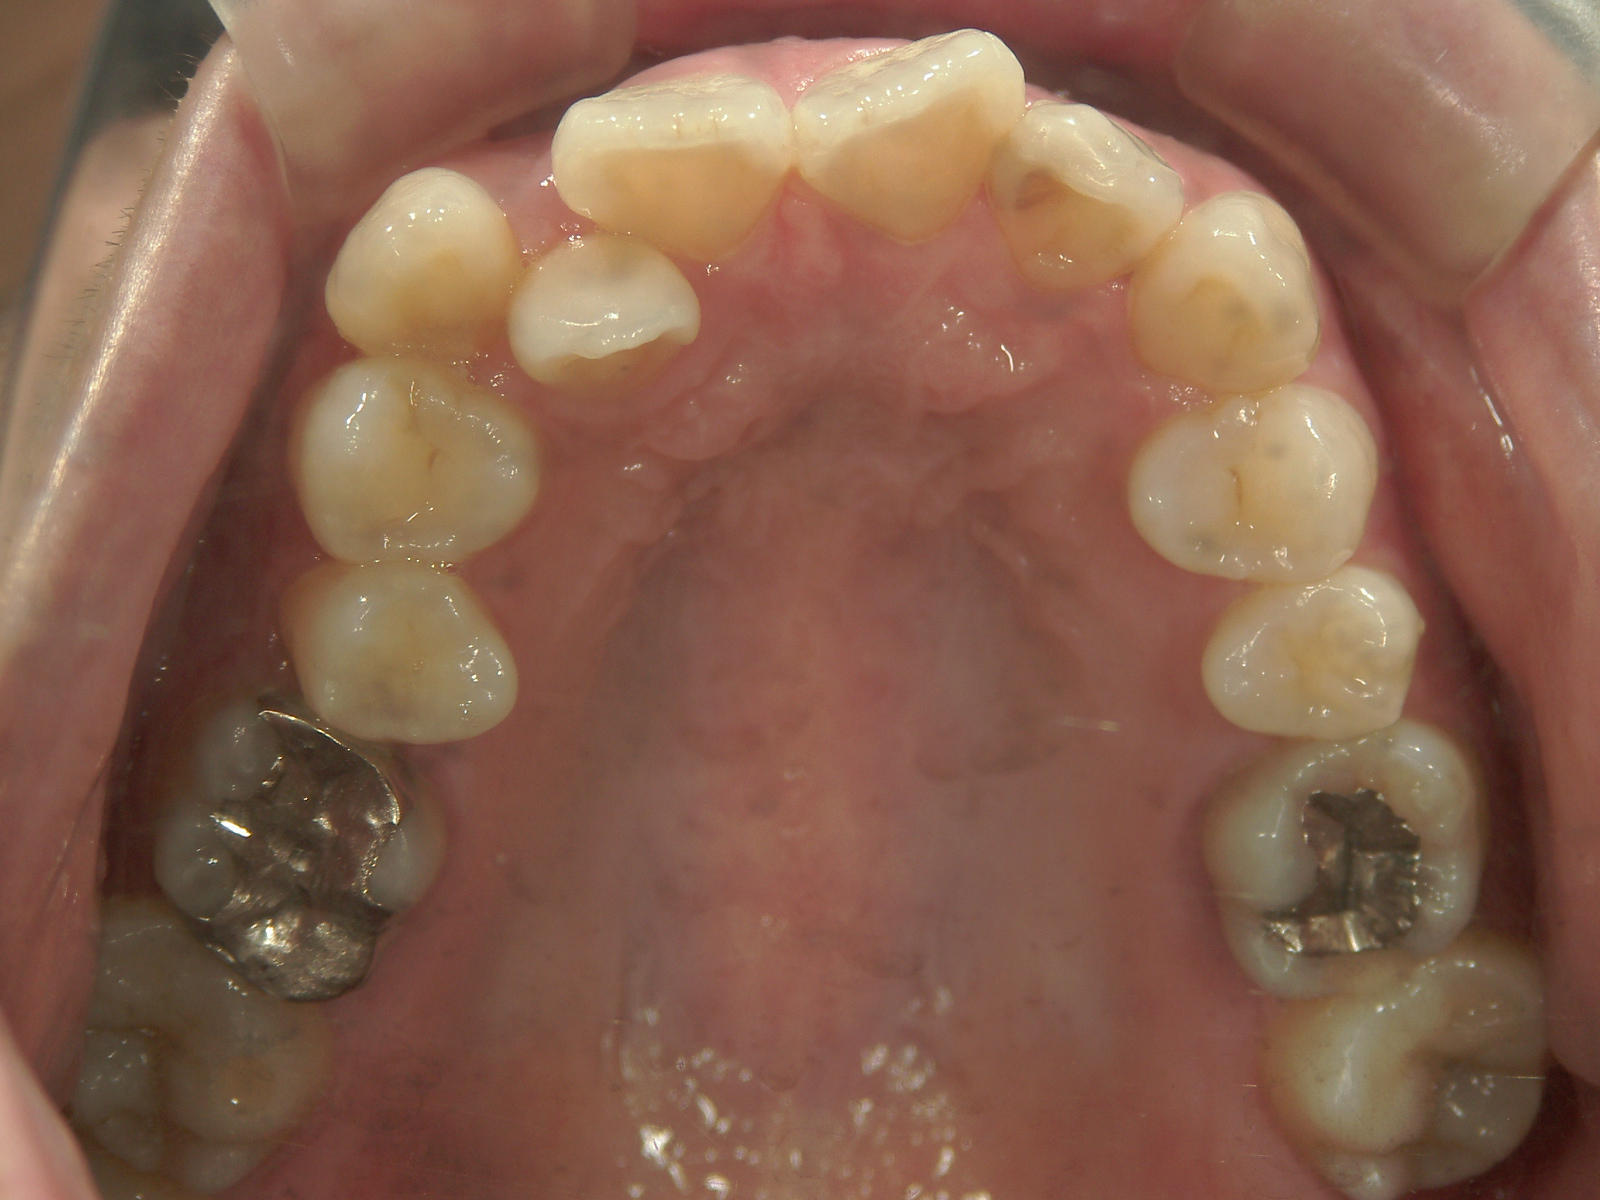

左右上 第一小臼歯(2本)、左右下 第二小臼歯(2本)を抜歯。

矯正装置(BH・QH)を併用。

ミニインプラント、アップライトスプリングを併用。

右下大臼歯(2本)をZ冠、E-MAX(On)に変更。